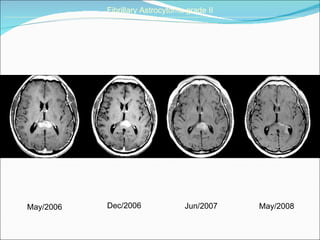

May/2006 Dec/2006 Fibrillary Astrocytoma grade II ______________________________________________________________________________________________________________________________________   May/2008 Jun/2007

May/2006 Dec/2006 FibrillaryAstrocytoma grade II ______________________________________________________________________________________________________________________________________ May/2008 Jun/2007